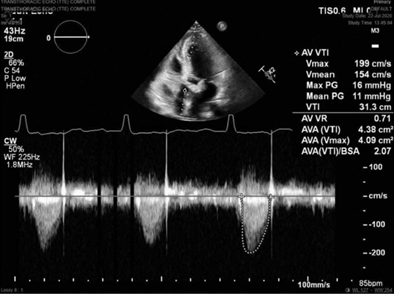

FIGURE 2 Representative predischarge transthoracic echocardiography image with continuous-wave Doppler demonstrating low postoperative aortic valve gradient and velocity in the KONECT RESILIA aortic valved conduit (Edwards Lifesciences, Irvine, CA).